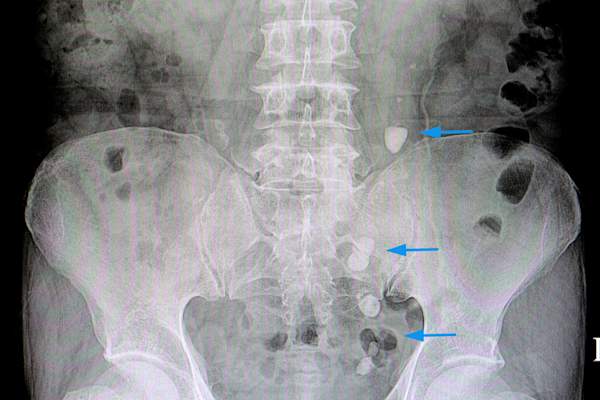

如果你已经通过手术切除了部分小肠,并且出现了短肠综合症的症状,你的医生可能会给你做检查,提供血液测试,或者检查你的粪便诊断的条件。在体检中,他们会检查体重减轻和维生素缺乏的迹象。验血可以显示你血液中的维生素和矿物质含量。粪便测试可以显示有多少脂肪和其他营养物质没有被你的身体吸收。有时会使用x光或CT扫描。

此外,你的电解质水平可能变得不平衡,从而引起肌肉的问题或不规则的心跳,或者您可以开发痛苦的肾结石。细菌可以在你的小肠生长失控(通常主机很少的细菌),引起腹泻或腹胀。